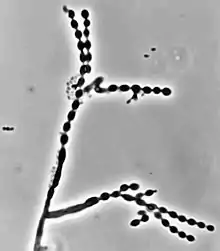

Cladophialophora carrionii is part of a group of melanized fungi, also known as “black yeasts” because its mycelial form has a dark green colour and its conidia have brown pigment.[2][6] Colonies grow at a modest rate on Sabouraud dextrose agar.[1] The conidia of C. carrionii are unicellular oval-shaped spores that are distinguishable due to the presence of two lightly pigmented scars.[6][7] Conidia vary in length (1.5-3.0 × 2.0-7.5 µm).[1] Its long conidiophores are similar to the genus Cladosporium, which comes from the Latin word "clado", meaning branched.[1] The genus Cladophialophora is distinguished from Cladosporium because in addition to chains of conidia, members of the genus Cladophialophora also produce phialides.[8] Cladophialophora carrionii is a dimorphic pathogen that changes states from a mycelial form to a muriform, yeast-like state once it invades its host.[3] Muriform cells are golden-brown in colour due to melanin deposition and have thick cell walls.[2][3]

Like many other black yeasts, C. carrionii is sensitive to temperatures above 37 °C.[6] It can be distinguished in culture by the presence of its urease enzyme hydrolyzing urea[9] and its inability to liquefy gelatin.[7][10] Altering temperatures or micronutrient levels such as calcium and phosphate affects whether C. carrionii is in the mycelial or muriform state.[2] The fungus transforms to muriform cells under conditions of temperature between 25 °C to 37 °C, 0.1 mM Ca2+, and a pH of 2.5.[8] It produces multiple conidia in long, straight chains that bud off the hyphae, with the youngest conidia farthest from the hyphae.[2] There is no sexual state known for C. carrionii.[6]